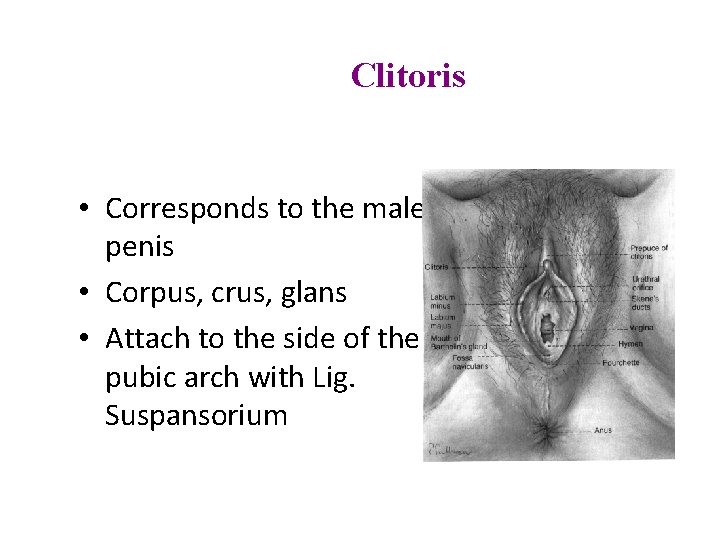

Clitoris • Corresponds to the male penis • Corpus, crus, glans • Attach to the side of the pubic arch with Lig. Suspansorium